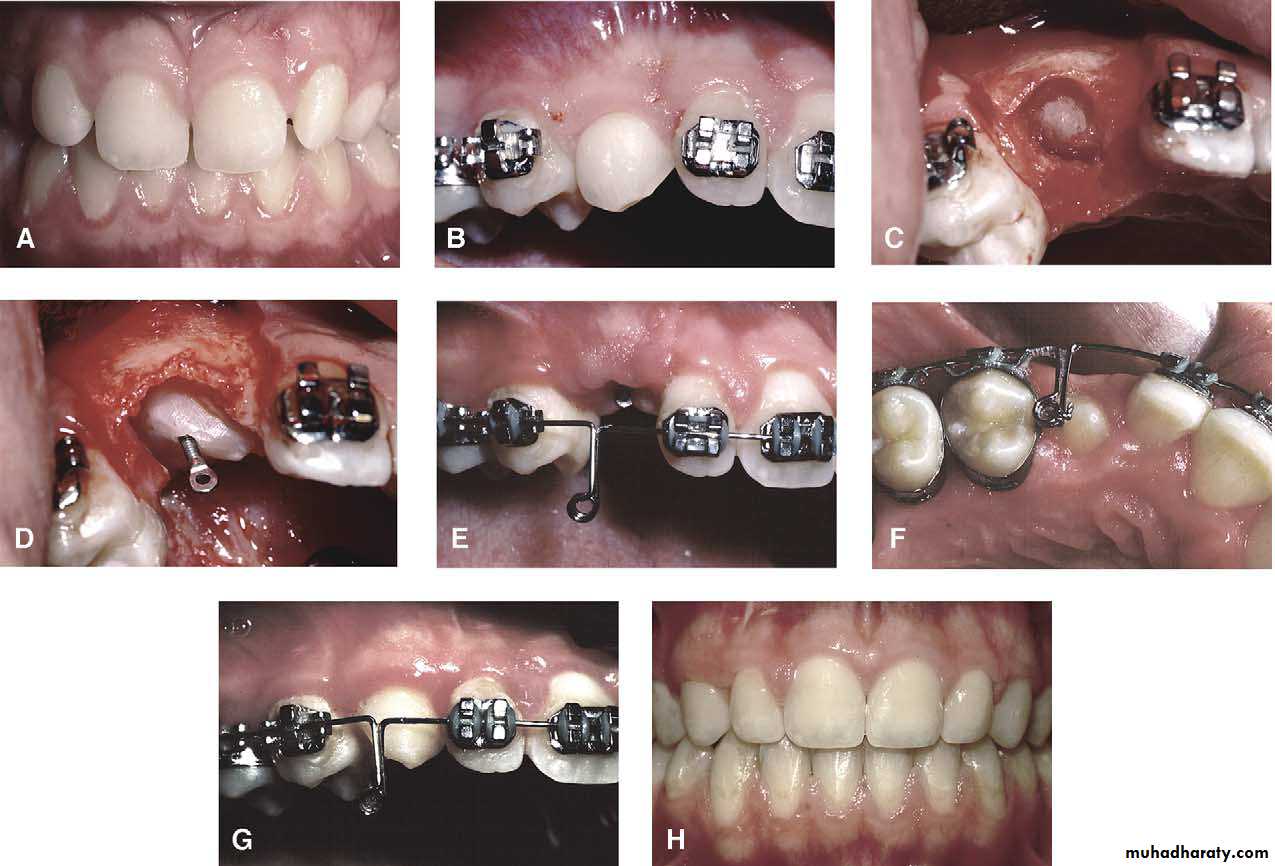

Surgical exposure

An attempt is made to assist the eruption of a malposed and unerupted canine into a functional position . It is considered when :1- there is adequate room in the arch to accommodate the tooth .

2- the potential path of eruption is unobstructed

3- exposure of the crown can be carried out as close as possible to the time at which normal eruption would occur .

Surgical exposure :the path of eruption is not obstructed

Surgical exposure with orthodontic traction: the path of eruption is obstructed

The initial stage of the operation is to reflect the mucoperiosteum and to remove the bone overlying the tooth to expose the greatest coronal diameter, the incisal edge and the cingulum . before repositioning the palatal flap a window is excised in it corresponding to the bony cavity containing the crown .the flap is then sutured as usual and a pack of iodoform gauze should be pressed firmly in to the bony defect so as to cover the exposed crown .

This pack should be held in position with suture and left insitu for 2-3 weeks to prevent granulation tissue and mucosa from overgrowing the denuded crown .after removal of the pack the progress of eruption should be observed at frequent intervals .

Following eruption of the tooth , orthodontic treatment may be required to guide it into a good position in the arch . Some times orthodontic traction is arranged at the time of surgery .

Transplantation and surgical repositioning

The success rate with transplantation is highest for unerupted teeth which have open apices because of the possibility of revascularization .It is essential to establish that there is sufficient space to accommodate the canine crown. minimal space deficiency may be overcome by grinding of the crown , but otherwise orthodontic therapy may be required to move the premolar distally .

The canine should be extracted carefully and transferred to the surgically prepared socket in the dental arch with the minimum of delay.

It is preferable that the root surface should not be touched either with instruments or fingers as the viability of the cementum and periodontal membrane remnants will determine the success of the transplant. The tooth is stored under the flap until the new socket is prepared .

Root filling is not attempted so as to reduce handling of the tooth . The transplanted tooth should be splinted in its new position for a month after the operation .